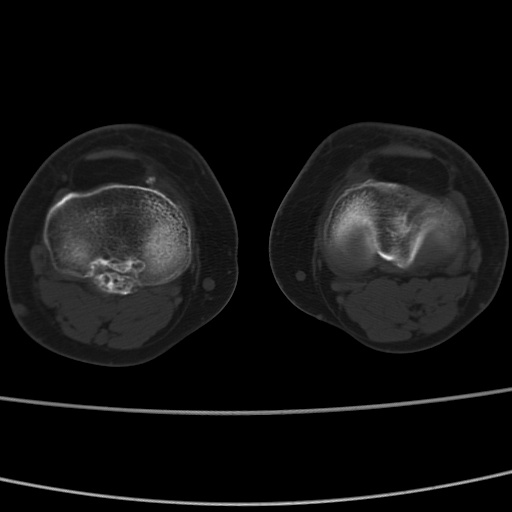

女性,50岁。【请提供患者临床症状体征】

右膝关节退行性改变,关节游离鼠。

右膝关节退行性改变,滑膜黏液囊钙/骨化并游离。